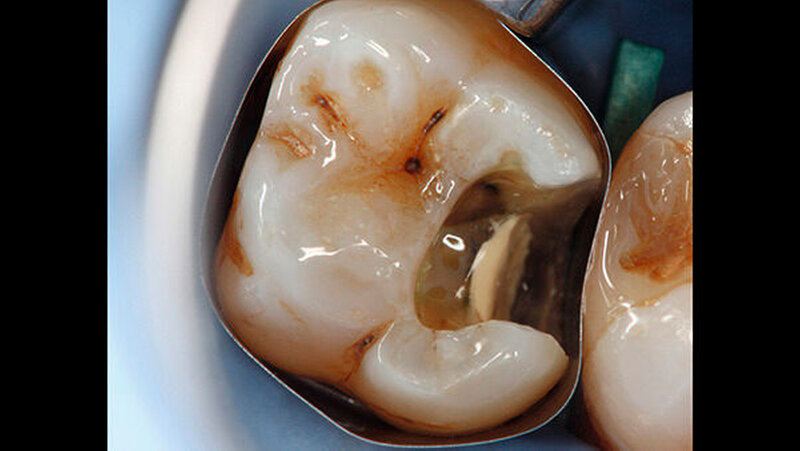

Ein 72-jähriger Patient stellte sich im Oktober 2013 zu einer Routinekontrolle in der Poliklinik für Zahnerhaltung und Parodontologie der Universität Regensburg vor. Bei der Befunderhebung wurde aufgrund des Verdachts auf Approximalkaries eine Röntgenaufnahme im Bereich des zweiten Quadranten angefertigt. Im Bereich des Zahns 26 distal wurde eine "Caries profunda“ diagnostiziert (Abbildung 1) und daher ein Termin zur Füllungstherapie vereinbart.

-Schnee war positiv. Die Behandlung wurde auf Wunsch des Patienten ohne Lokalanästhesie durchgeführt. Vor der Präparation erfolgte das Anlegen von Kofferdam an den Zähnen 24 bis 27. Zunächst wurde mit rotierenden Diamantschleifern unter Wasserkühlung von okklusal ein Zugang zum Defekt geschaffen. Der distale Kavitätenbereich wurde mit oszillierenden Instrumenten präpariert (SonicFlex, KaVo) (Abbildung 2). Dabei wurde die Kavität so zierlich wie möglich gestaltet.